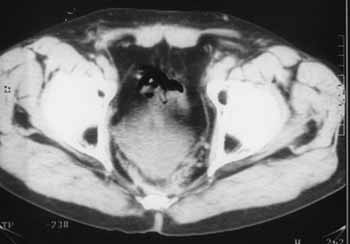

Рис. 2. Через 2 года после операции отмечается деформация и смещение кзади мочевого пузыря, фиброзные изменения предсакральной клетчатки. Рецидива нет.